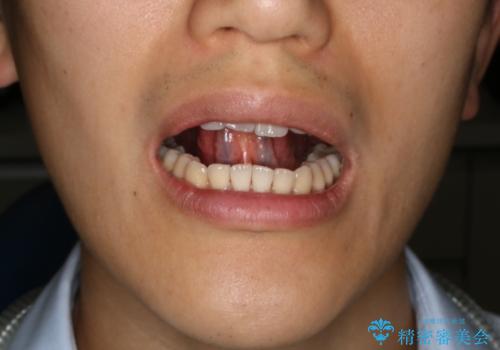

- ご自身の滑舌の悪さを主訴に舌小帯切除術を希望され、来院されました。

手術とともにMFT(口腔筋機能療法)を行うことの重要性を説明させていただき、ご理解いただき並行して進めていくこととなりました。

舌の下に繋がる靭帯を舌小帯といい、人によって長さや硬さなどの条件が異なります。舌小帯が短かったり硬くなってしまうと、舌の運動が制限されてしまい滑舌や摂食・嚥下に影響を及ぼすことがあります。

このような場合に適用される手術を「舌小帯切除術」といいます。

今回のケースではレーザー機器を用いて手術を行いました。これにより従来のメスを使用する術式と比べて所要時間の短縮が図れ、かつ縫合を必要としないため術後の不快感も軽減することができます。